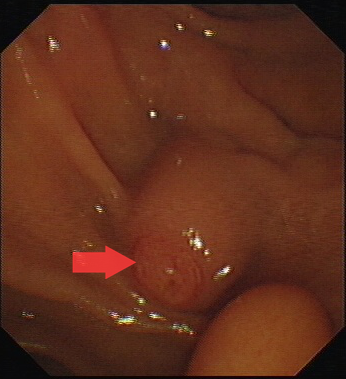

圖一:十二指腸乳頭。

第一步,先將十二指腸鏡到達十二指腸乳頭處,將通過十二指腸乳頭進入膽總管取石